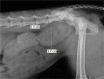

Figure 2

Right lateral caudal abdominal radiograph (initial referring practice radiographs). Colonic diameter 3.7 cm. Ratio of colonic diameter to L5 length is 1.61, compatible with megacolon (a ratio >1.48 is suggestive of megacolon, according to Trevail et al)